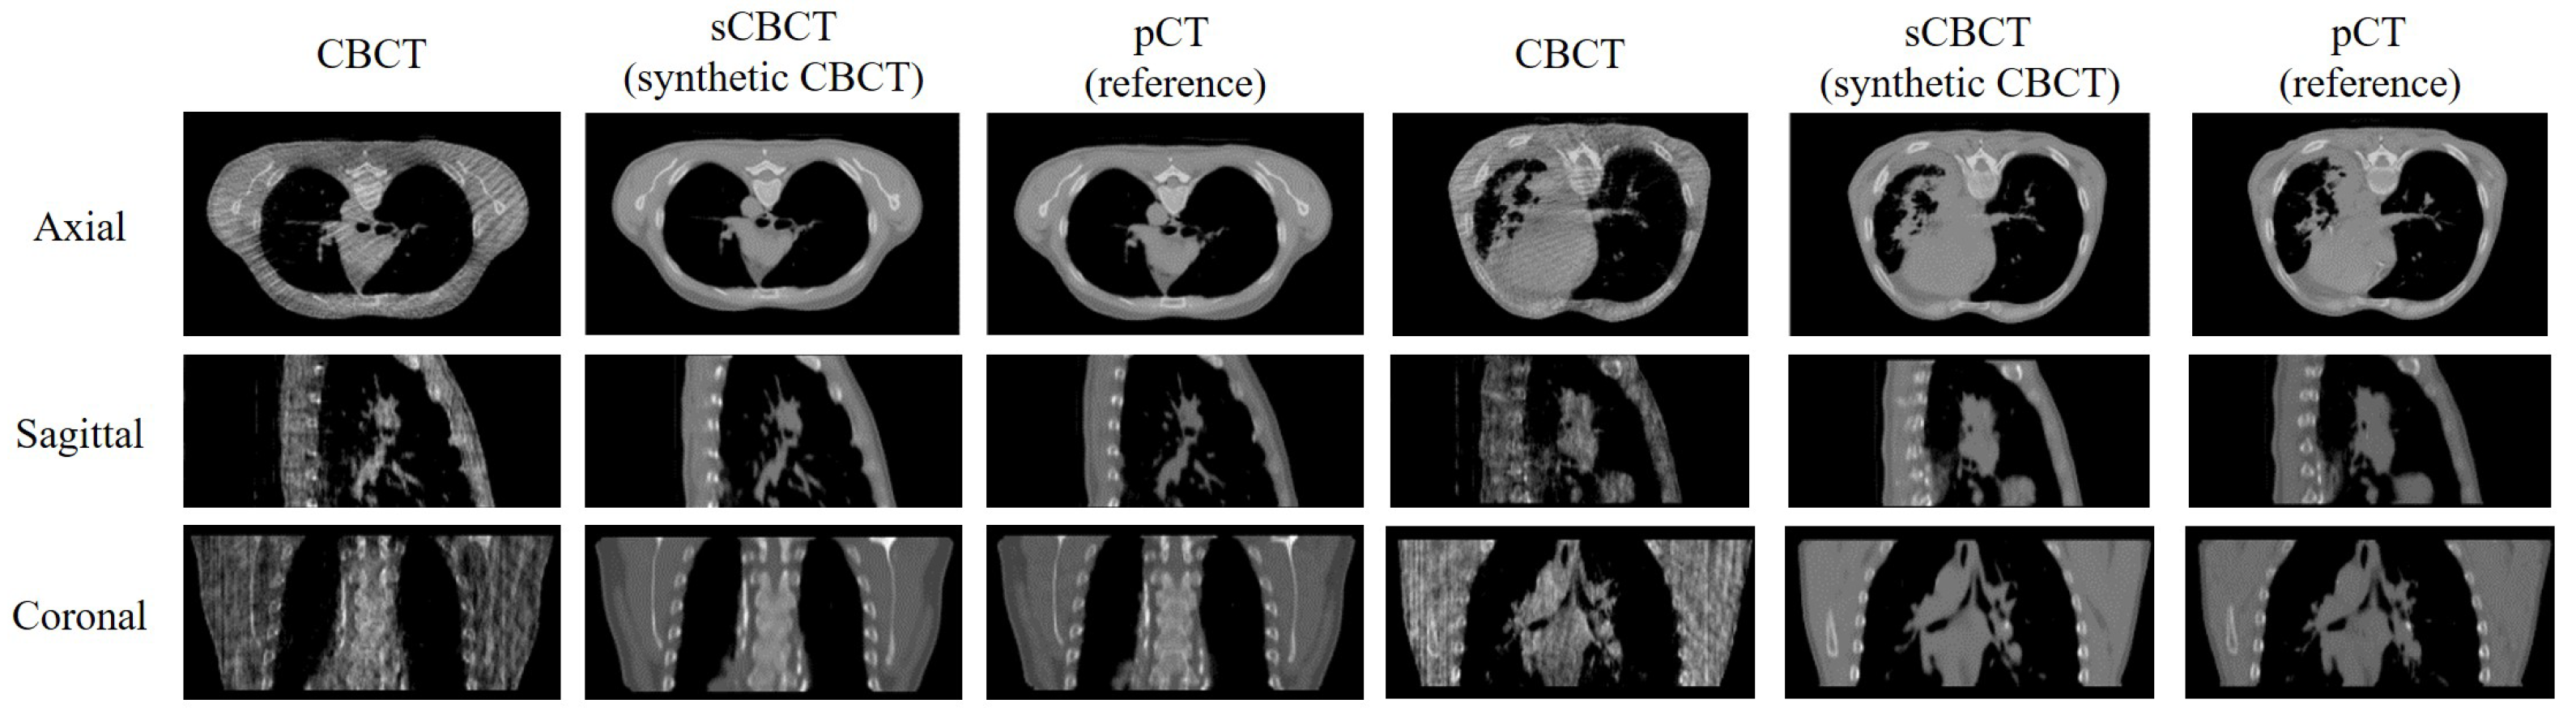

| Data | Image Types | MAE↓ | RMSE↓ | PSNR↑ | SSIM↑ |

|---|---|---|---|---|---|

| Patient 1 | sCBCT-pCT | 18.496 | 60.093 | 30.662 | 0.926 |

| Patient 2 | sCBCT-pCT | 18.319 | 59.662 | 30.753 | 0.927 |

| Patient 3 | sCBCT-pCT | 20.803 | 67.172 | 30.263 | 0.921 |

| Patient 4 | sCBCT-pCT | 19.852 | 63.899 | 30.196 | 0.923 |

| Mean | sCBCT-pCT | 19.398 | 62.707 | 30.469 | 0.924 |

| CBCT-pCT | 49.945 | 117.803 | 24.540 | 0.811 |